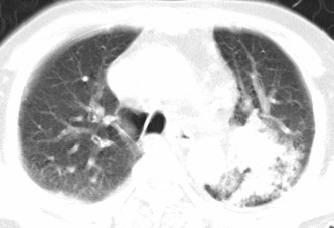

以下是引用xianxianzhongyi在2008-4-20 14:44:00的发言:[br]本人愚见:次病例短短两月的时间,呈现如此大面积实变,病变增长过于迅速,此其一。其二,病变在动脉早期既有明显强化。其三,左上叶后段及下叶背段多叶受累。其四,肺门及纵隔内未见明显肿大的淋巴结。估计层面较厚段支气管显示不清。 诊断:炎性实变可能性大。

以下是引用光影相伴在2008-4-20 14:39:00的发言:[br]支持:1)左侧中央型肺癌伴左肺上叶阻塞性肺炎。、[br] 2)双侧少量胸腔积液。